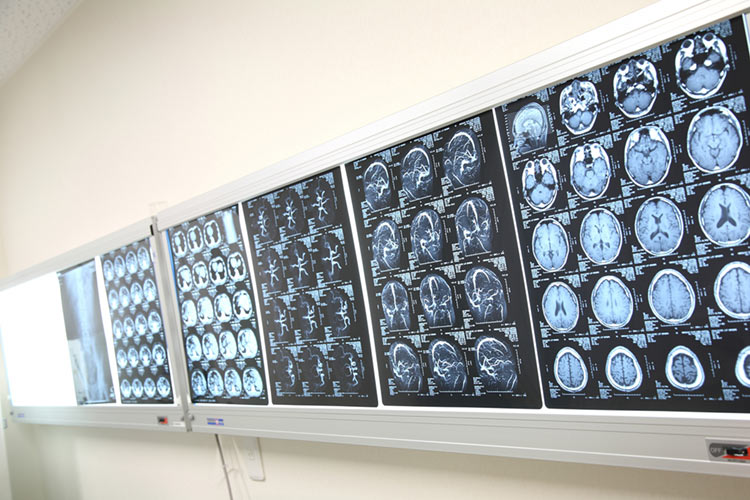

16列マルチスライスCTを導入しています

当院では、最新の16列マルチスライスCTスキャナを導入しているため、詳細な頭部の検査を行うことができます。この装置は1回の撮影で16列の断面を同時に撮影できる高水準のマルチスライス技術を搭載しています。検査時間は従来の機器よりも短縮されており、迅速に検査していきます。被曝量も40%ほど低減されているため、患者さまへの負担も大幅に軽減することができます。